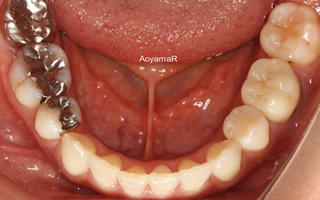

そう生(歯並びのガタガタ、乱杭歯、八重歯)の矯正症例

CASE 17

(38歳 女性 )

上下第一小臼歯抜歯による叢生改善

マウスピース型カスタムメイド矯正装置(インビザライン)単独による治療

治療前